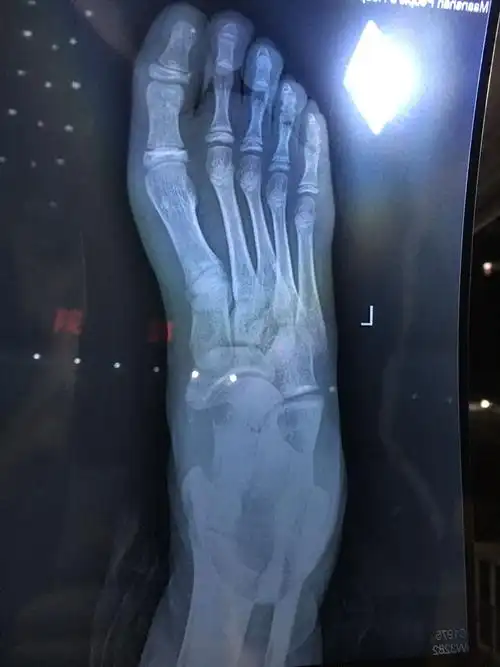

医生,我脚前天被叉车轮胎压了导致第二脚趾骨折,前天,昨天都打

脚骨折第二天